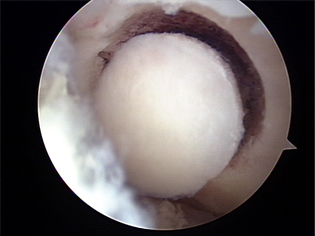

자가연골이식술 1

자가연골이식술 2

자가연골이식술 3